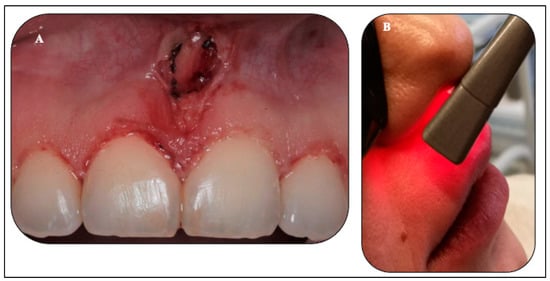

2.5.2. Upper Midline Frenectomy Procedure

2.5.3. Transcutaneous λ940 nm Laser-PBM (Extraoral Approach)